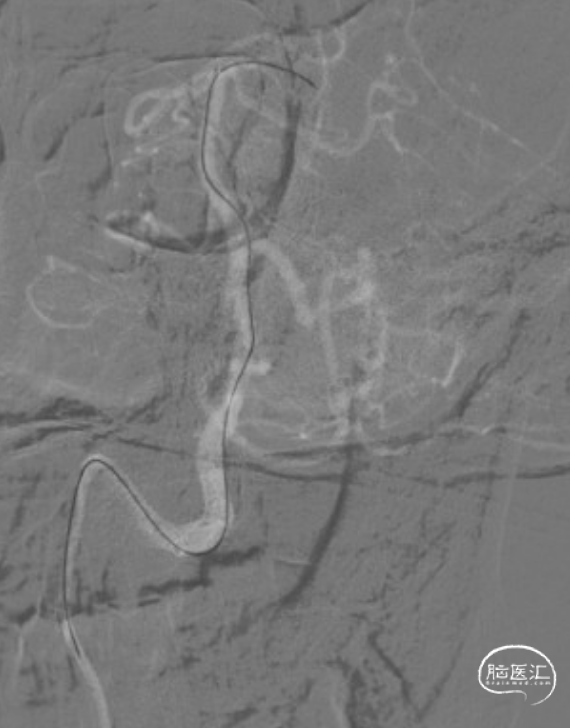

赛诺NOVA®颅内药物洗脱支架 2.75*12mm输送至病变段。

10atm压力释放赛诺NOVA®颅内药物洗脱支架。

术后造影:RV4段狭窄较前明显改善。